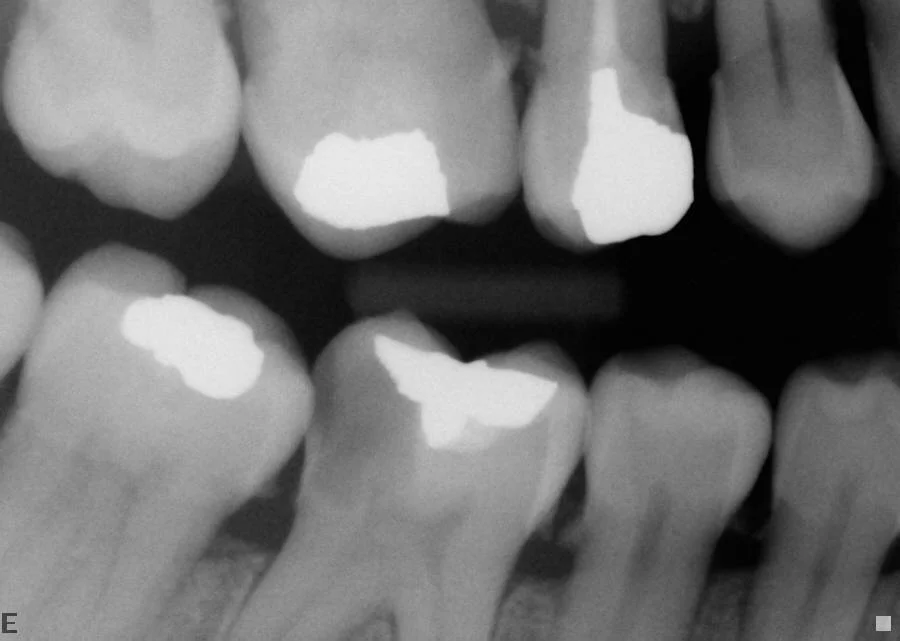

A lower molar has been extracted years ago and not replaced—leading to extensive over-eruption and tilting of the remaining teeth. This opens up contact points leading to food packing, decay, irregular bite and loss of further teeth. Always replace missing lower molars as soon as possible.